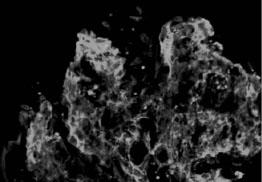

光镜下,大多数患者肾小球呈内皮细胞、系膜细胞弥漫性急性增殖,少数以渗出病变为主,另有少部分呈系膜、毛细血管型病变(膜增殖型病变),严重时增生的系膜可将肾小球分隔成小叶状,偶有球囊新月体形成。电镜可见上皮下电子致密物呈驼峰状沉积,为本病的特征。但这一变化消失较快,发病3个月后即不易见到,这些沉积物多在上皮侧,有时在内皮下。免疫荧光检查,内含有免疫球蛋白,主要是IgG、IgM、IgA也可见到,同时也可有C3沉积,有时尚可见到链球菌抗原在系膜区沉积物中。见图2—1、图2—2、图2—3。

图2—1 毛细血管内增生性肾小球肾炎,肾小球内皮和系膜细胞增生,中性粒细胞浸润(PASM x400)

图2—2 毛细血管内增生性肾小球肾炎,上皮下有驼峰状电子致密物沉积(电镜 x6800)

图2—3 毛细血管内增生性肾小球肾炎,IgG呈颗粒状沉积于毛细血管壁(免疫荧光 x400)